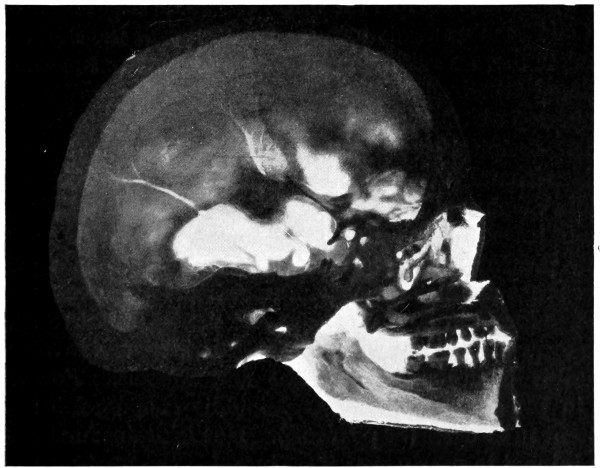

29 A and B. The base of the skull and the base as seen on transillumination 70, 71

43 A and B. An explosive fracture of the vault of the skull 113

50 A and B. The inner aspect of the skull and the same seen on transillumination 137